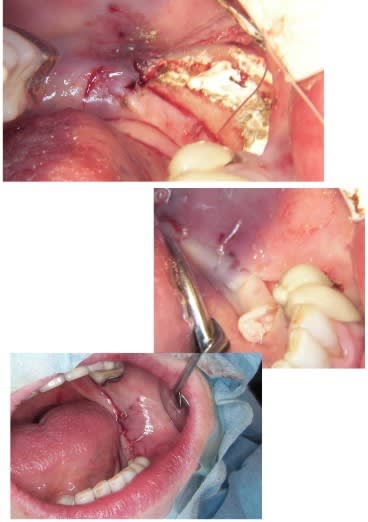

Je mets les coupes scan et tu comprendras son hésitation

pour ce vendredi, expansion verticale en bas à gauche, pas simple mais...

Implants à gauche et à droite, c’est un cas d’expansion horizontale droite et gauche que je dois faire en Novembre en directe (pour des confrères Russes), et vendredi je prépare le site à gauche, pour avoir une hauteur correcte pour remplacer ensuite 35/36.37.

En principe je ne poserais pas les implants vendredi, sauf si le site est nickel pour.

bon ça c'est fait!